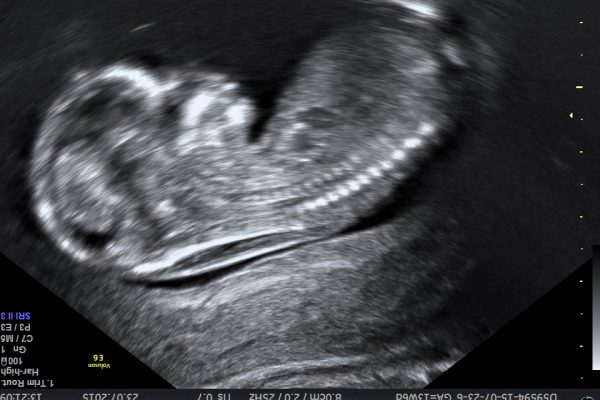

- 3D/4D ultrazvučni pregled ploda, tzv. anatomy scan